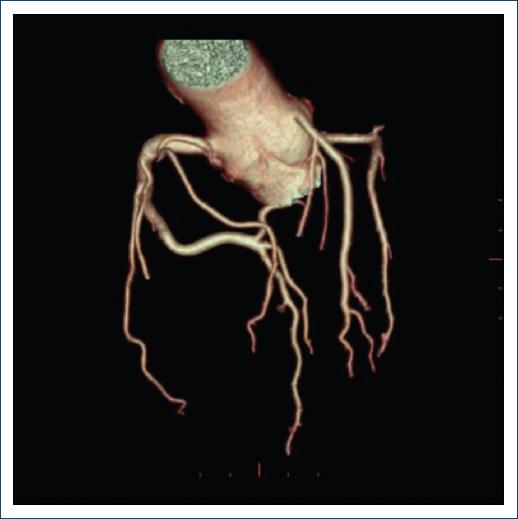

Un paciente estudiado por enfermedad de Kawasaki tenía nacimiento anómalo de la ACX del seno coronariano derecho con trayecto retroaórtico y aneurismas en la ACD y DA (Fig. 2).

Figura 2 Imagen en volumen rendering del árbol coronario, donde se observa naciendo del seno coronariano derecho (de manera independiente) las arterias coronarias derecha, descendente anterior con trayecto por delante del tracto de salida ventricular derecho y arteria pulmonar y arteria circunfleja con trayecto retroaórtico. De manera independiente naciendo del seno coronariano izquierdo el ramo diagonal y septales.